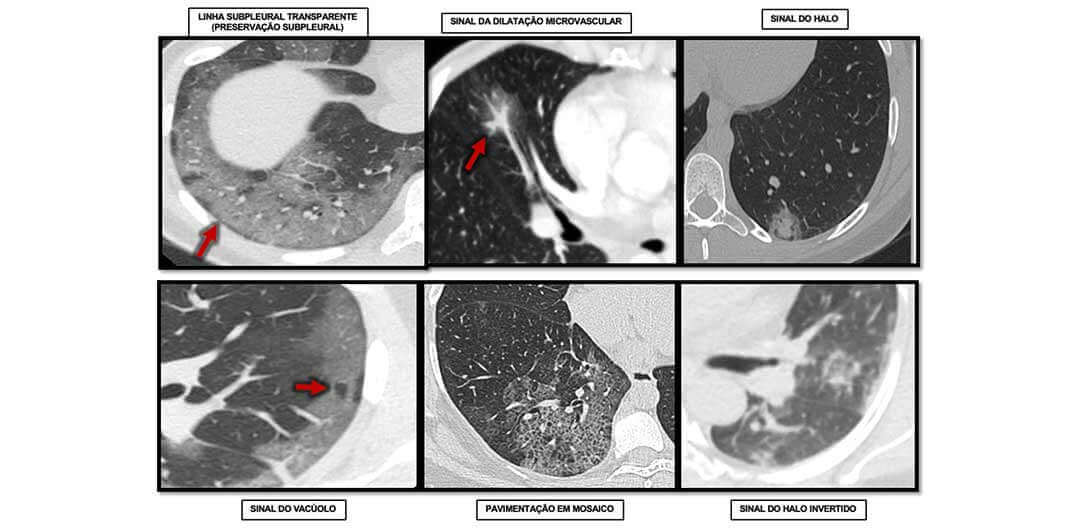

Sinais radiológicos na COVID-19: Existem?

Estudo sugere que tomografia computadorizada é melhor que teste de laboratório para diagnosticar COVID-19